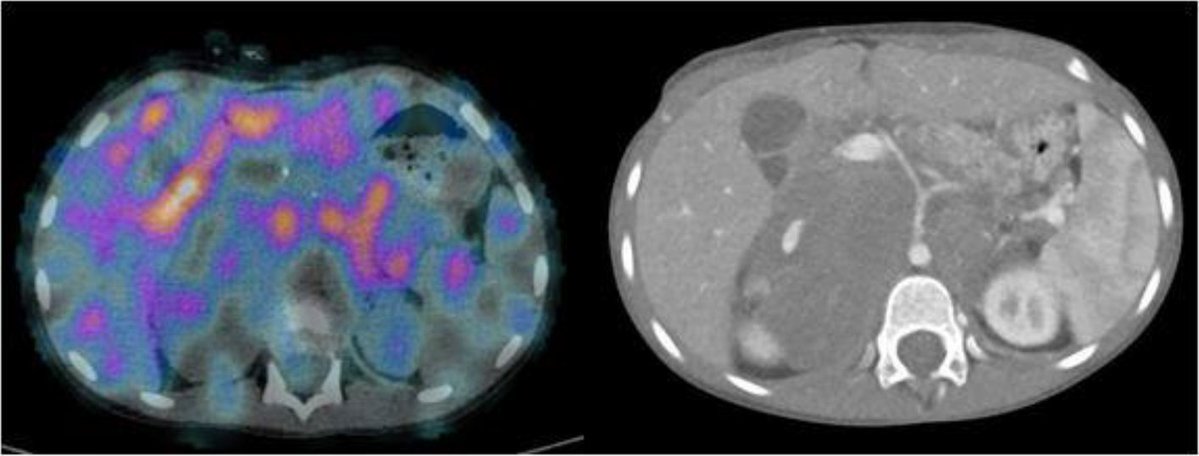

Read one of our latest published papers focusing on electrochemotherapy as a potential local treatment for residual MIBG-avid disease in refractory pediatric neuroblastoma: a case report

link.springer.com/article/10.100…